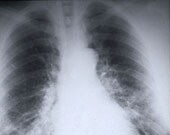

Palliative Radiotherapy Often Overused in Stage IV NSCLC

Not proven to further improve symptoms or quality of life; can have significant side effects